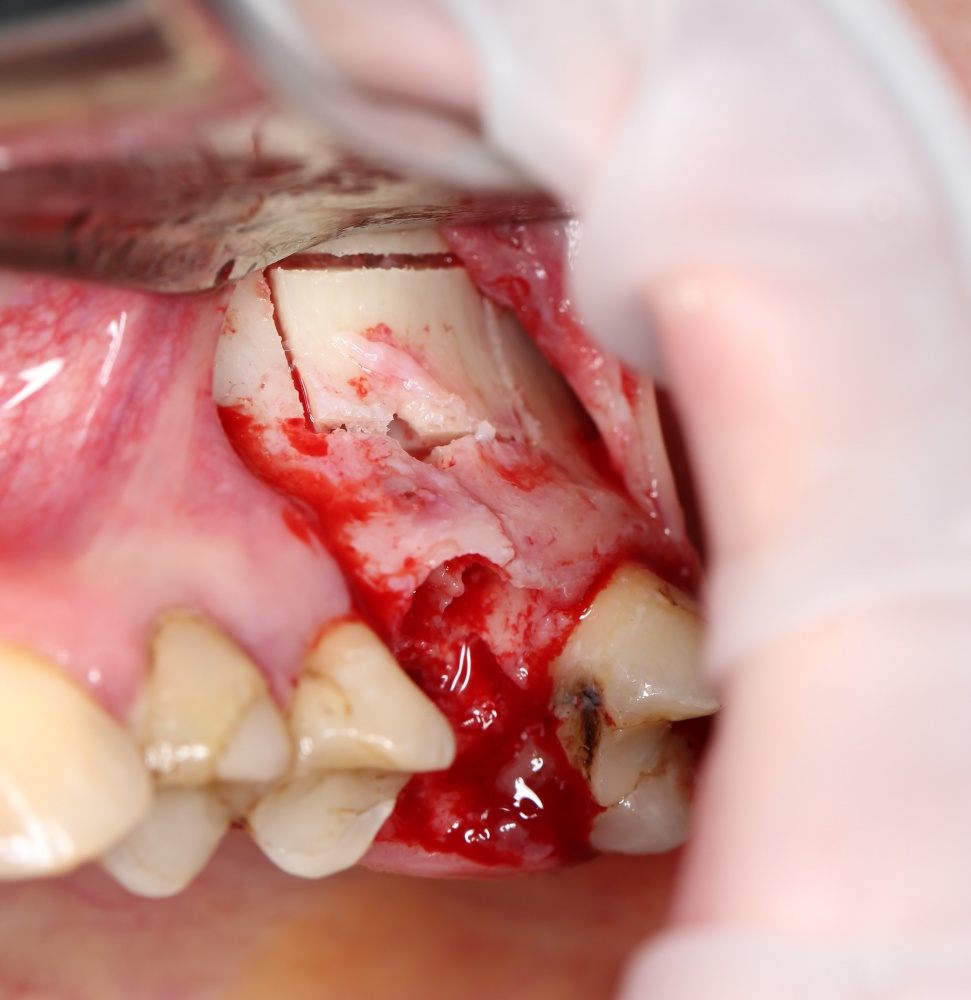

Простой синуслифтинг. Часть I.